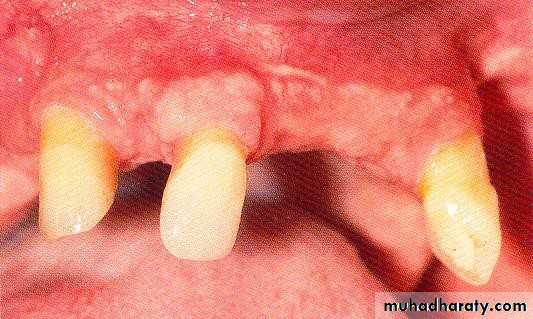

• 1) Few remaining teeth or teeth with an unfavourable distribution in the arch which precludes treatment with a removable P.D.

• 2) Severe loss of periodontal attachment in a patient who cannot afford a fixed partial denture

• 3) Complicated functional and aesthetic conditions due to tooth migration which make restoration with a removable or fixed partial denture difficult.